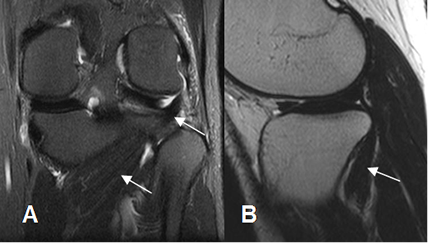

Este ligamento está rodeado por los ligamentos meniscofemorales que se originan del cóndilo femoral interno y se insertan en el menisco externo. Son el anterior o de Humphrey y el posterior o de Wrisberg. Estas estructuras no deben confundirse con cuerpos libres intra-articulares. (2). (Fig 18 y 19).

Fig 18. Ligamentos meniscofemorales.

A y B: RM sagital en T1. Ligamento meniscofemoral anterior (Flecha delgada) y posterior (Flecha gruesa).

Fig 19. Ligamentos meniscofemorales normales.

A: RM coronal en T1 y B: RM coronal en STIR. Ligamento menisco femoral posterior (Flecha delgada), en relación con el LCP (Flecha gruesa). Menisco externo (Punta de flecha).